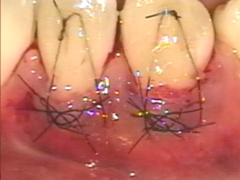

歯周再生治療~カンガルーテクニック~

切断された歯肉を再生することを目的とした治療です。

歯間乳頭の剥離は行いません。

カンガルーテクニック症例1

治療前

治療前 治療後

治療後

◆治療内容

切断された歯肉を再生することを目的とした治療です。 歯間乳頭の剥離は行いません。

◆リスク

・感染リスクが高まる

・瘢痕による審美性の悪化

◆治療費

保険適用外 20,000円 (税別)